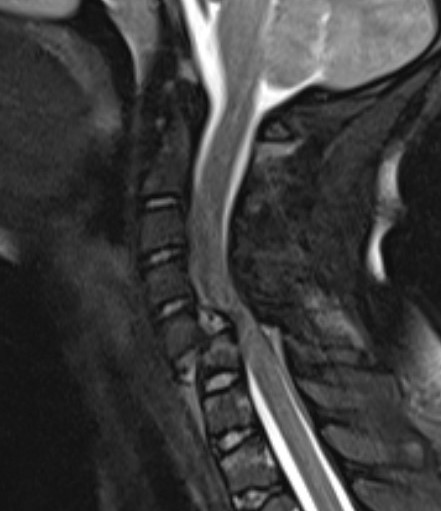

Neurological outcome

MRI post reduction and ACDF demonstrating spinal cord injury

- closed or open reduction and fixation

- unilateral facet: 62% improved one or more grade, 24% improved two or more grades

- bilateral facet: 57% improved one ore more grade, 13% improved two or more grades